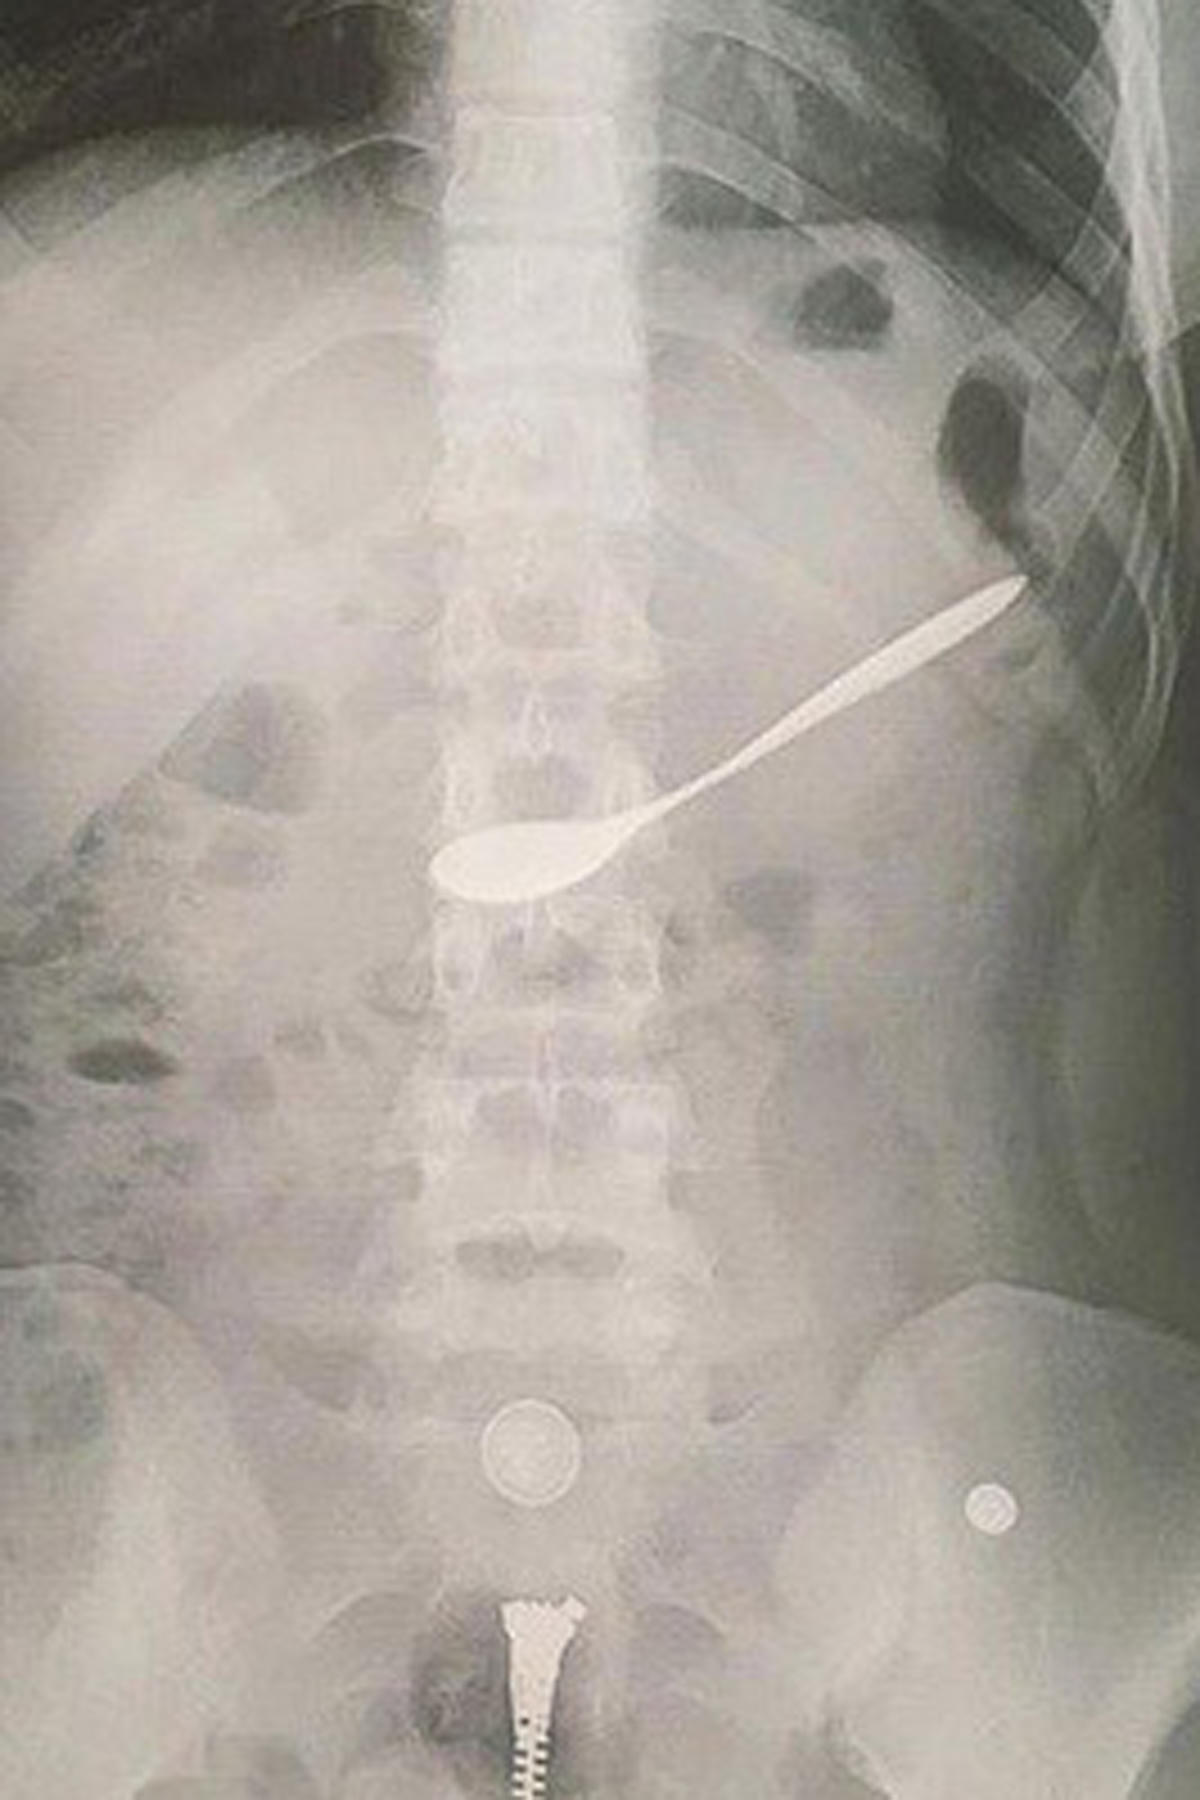

(PLO) -Trong lúc ngồi uống cà phê với bạn, một cô gái trẻ ở TP Vinh (Nghệ An) không may nuốt cả chiếc thìa bằng kim loại vào dạ dày.

Theo thông tin ban đầu, trong lúc đi uống cà phê với bạn, một cô gái trẻ trú tại TP Vinh đã không may nuốt chiếc thìa pha cà phê bằng kim loại vào trong dạ dày. Ngay sau khi sự việc xảy ra, những người bạn đi cùng đã nhanh chóng đưa cô gái tới Bệnh viện Đa khoa TP Vinh cấp cứu.

Ông Nguyễn Hồng Trường, Giám đốc Bệnh viện Đa khoa TP Vinh, tỉnh Nghệ An cho biết: "Sau khi tiến hành nội soi, các bác sĩ của bệnh viện đã gắp chiếc thìa ra khỏi người bệnh nhân"

Sau khi chiếc thìa bằng kim loại được gắp ra ngoài, bệnh nhân đã hồi phục sức khỏe.